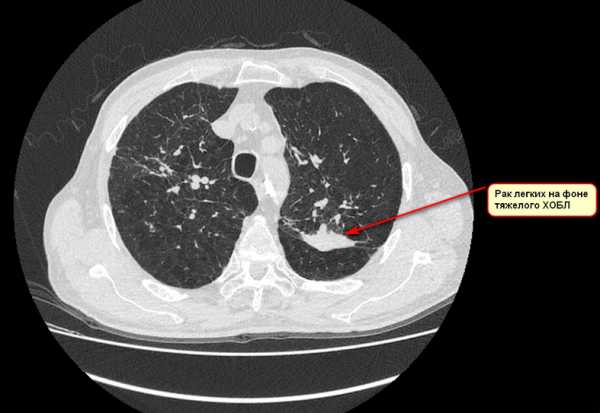

Мужчина , 54 лет, курильщик. Жалобы на небольшой кашель. При флюорографии патологии легких выявлено не было. Однако сохранявшийся кашель инициировал у пациента пройти Пульмонологическое обследование. При КТ легких (фото №1) выявлено субсолидное образование на фоне «матового стекла», которое при динамическом мониторинге (фото №2) увеличилось в размерах. При проведение ПЭТ КТ подозрение на злокачественную природу новообразования усилилось. При проведении морфологической верификации была выявлена злокачественная аденокарцинома. Пациент успешно проопериован.